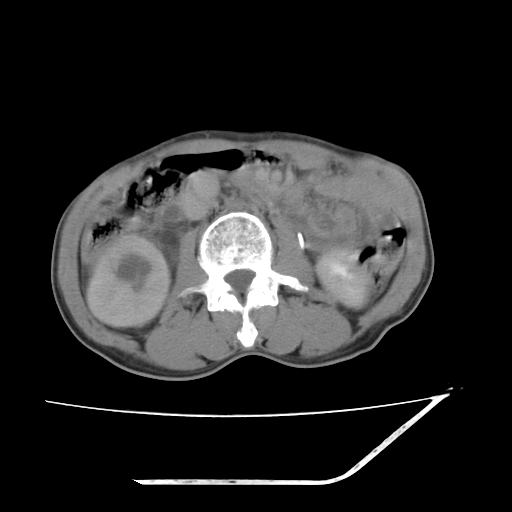

增强

考虑右肾盂癌,肾动脉受侵,右肾功能减退,右肾盂输尿管积水,管壁增厚,考虑种植转移,应该把下面扫完的

支持右侧肾盂癌伴肾静脉瘤栓形成可能性大,右肾结石.肝右叶后段低密度影,不除外转移.

考虑右肾盂癌,肾动脉受侵,右肾功能减退,右肾盂输尿管积水,管壁增厚,考虑种植转移  支持

右肾盂旁ca并肾静脉瘤栓形成/肾功能降低。

右肾结石。

右肾盂癌,肾动脉受侵,右肾盂输尿管积水,管壁增厚,考虑种植转移

支持 右侧肾盂癌伴肾静脉瘤栓形成可能性大,右肾结石;肝右叶后段低密度影,不除外转移。

1.右侧肾盂癌伴肾盂积水。

2.肾脏功能减退,原因有:(1)肾动脉受侵。(2)肾静脉受侵(3)肾积水,等。本例,肾动脉显影较好,但受压明显;肾静脉无明显显示,受压或静脉癌栓,下腔静脉腔内未见明显充盈缺损。

3.右侧上段输尿管扩张,原因:(1)积水所致;(2)种植。